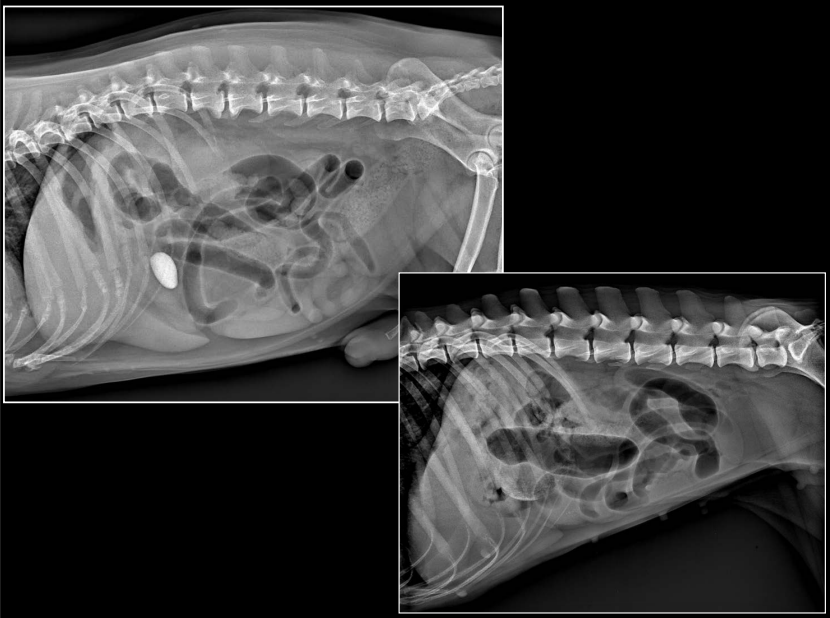

INTESTINO DELGADO

(Imagen: perro y gato comparativos.)

RX:

- Dos poblaciones de asas (normales / dilatadas)

- Diámetro aumentado

- Asas distendidas, paralelas

OBSTRUCCIÓN MECÁNICA

(Cuerpo extraño / invaginación / masas)

Importante saber a que diametro se considera que las asas han incrementado.

PERRO: diámetro normal I.D / L5 < 1,4

GATO: diámetro normal I.D / L2 < 2

OTRAS ALTERACIONES

- Inflamación

- Neoplasia

- Intususcepción